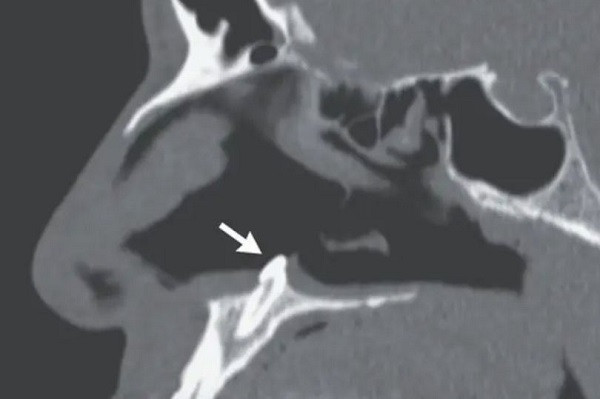

| Hình ảnh chụp cắt lớp phần mũi bệnh nhân. Ảnh: The New England Journal of Medicine |